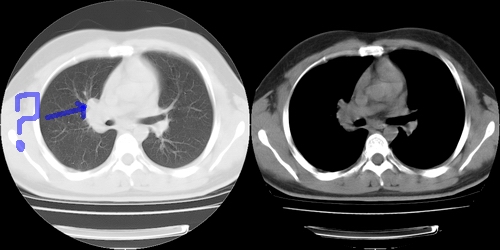

患者 男性 25岁,体检觉得右肺门感觉增大,请会诊,有没有异常?(我科诊断:未见异常)

右肺门增大,囊状影与肺动脉分支有关,上叶支气管受压移位。

考虑发生于右肺动脉分支的肺动脉瘤。

右主支气管及右中叶支气管受压,腔静脉后淋巴结肿大,不知肿块是血管还是淋巴s

右肺门前方[右侧上叶支气管尖后段分支水平]结节灶,隆突前似有淋巴结显示。结核或肿瘤。建议增强检查

建议增强,右肺上叶前段支气管受压变细,腔静脉后方见肿大淋巴结.考虑结节病或肺门占位.